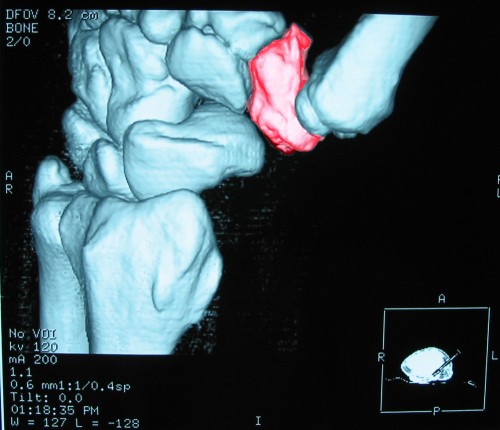

In anestesia locale, attraverso una piccolissima incisione che non necessita nemmeno di punti di chiusura, si introduce a livello ascellare la fibra laser del diametro di 0,6 mm. che provoca lo scioglimento del tessuto sottocutaneo all’interno del quale sono contenute la ghiandole sudoripare, provocandone la loro distruzione in maniera definitiva e permanente.